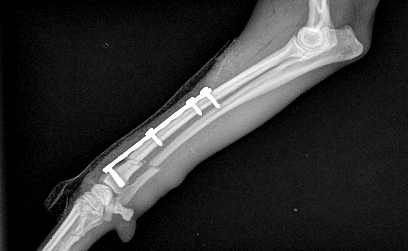

Le diagnostic est ensuite confirmé par radiographie

Le traitement de choix des fractures du radius et de l’ulna chez le chien est la chirurgie, en installant une plaque et des vis sur la fracture, pour maintenir les deux bouts de l’os bien en contact et alignés : un bon alignement et un bon contact, avec une immobilisation du membre pour permettre à l’os de se reconstruire sont les points essentiels à une bonne cicatrisation. Pour certaines fractures, il faut utiliser un matériel très particulier (plaques et vis verrouillées) pour s’assurer d’un résultat optimal et d’une cicatrisation parfaite.

Un suivi est réalisé par la réalisation régulière de radiographies (toutes les 3 à 4 semaines) jusqu’à cicatrisation complète.